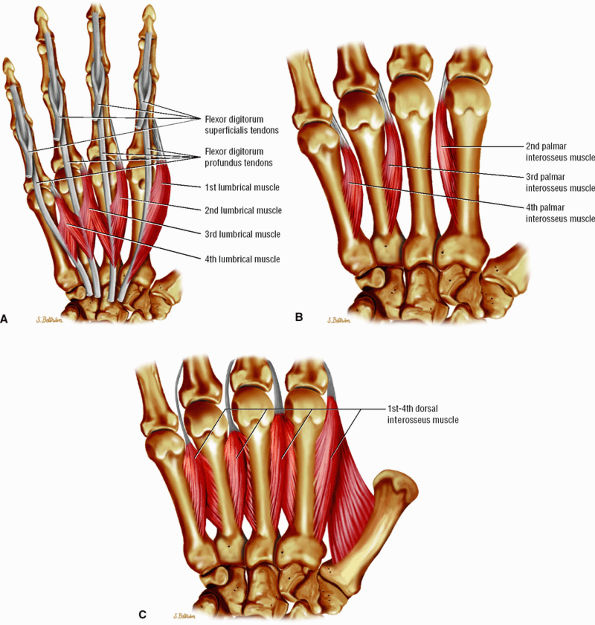

FIGURE 11.24 ● Intrinsic muscles of the hand. (A). Palmar view of the most common configuration of the lumbrical muscles. (B) Palmar view of the palmar interossei muscles. (C) Palmar view of the dorsal interossei muscles.